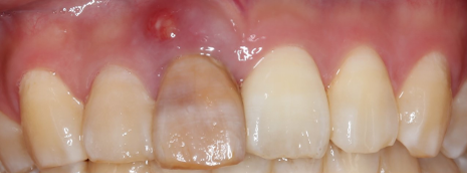

前歯が腫れてしまったと来院された患者様です。

レントゲンを見てみると歯根(歯の根の部分)が黒く溶けていることが分かり、抜歯と診断しました。

前歯のインプラントはとても難しく技術がないと歯茎が下がってしまったりと不具合が出てしまいます。

処置後、非常に審美的な補綴物が入ったことが分かるかと思います。